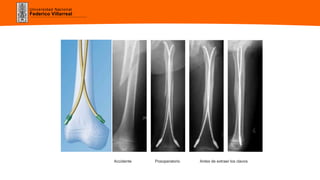

Enclavado Endomedular Elástico

(Métaizeau)

Preservación de los cartílagos de crecimiento.

Propiedades mecánicas que favorecen la

consolidación.

Ablación al 2° o 3er mes.

Accidente Posoperatorio Antes de extraer los clavos